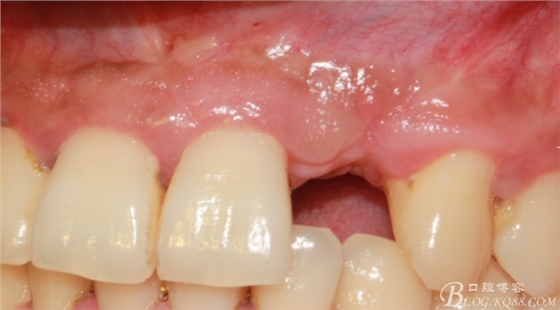

10天拆線一切正常,又過了兩周患者復(fù)診,自述期間無異常??趦?nèi)檢查,真的嚇了一跳,唇側(cè)鼓了個(gè)包,擠壓有白色分泌物溢出,絕對不是膿液,液體排除后,術(shù)區(qū)觸診空虛,外觀塌陷。這時(shí)候考研大夫的時(shí)刻到了,是先觀察一段時(shí)間再說?還是馬上進(jìn)行處理?我的回答是:馬上處理!如果你沒有及時(shí)處理,而是放患者回家觀察,那么接下來會(huì)發(fā)生如下情況:1.回家后患者家屬及親友會(huì)有很多你可以想象得到的討論;2.患者及家屬會(huì)對你產(chǎn)生不信任,勢必會(huì)到其他門診或醫(yī)院檢查,他院大夫會(huì)不會(huì)發(fā)表對你不利的言論;3甚至?xí)蚁嚓P(guān)法律界人士找你討要說法。

于是我果斷告知患者,手術(shù)失敗了,不能拖延,如不及時(shí)處理,炎癥繼續(xù)發(fā)展會(huì)很快波及鄰牙牙槽骨。患者接受我的建議。切開翻瓣,骨粉及生物膜消失了,骨吸收嚴(yán)重,幸運(yùn)的是,因?yàn)樘幚砑皶r(shí),鄰牙骨支持依然存在。